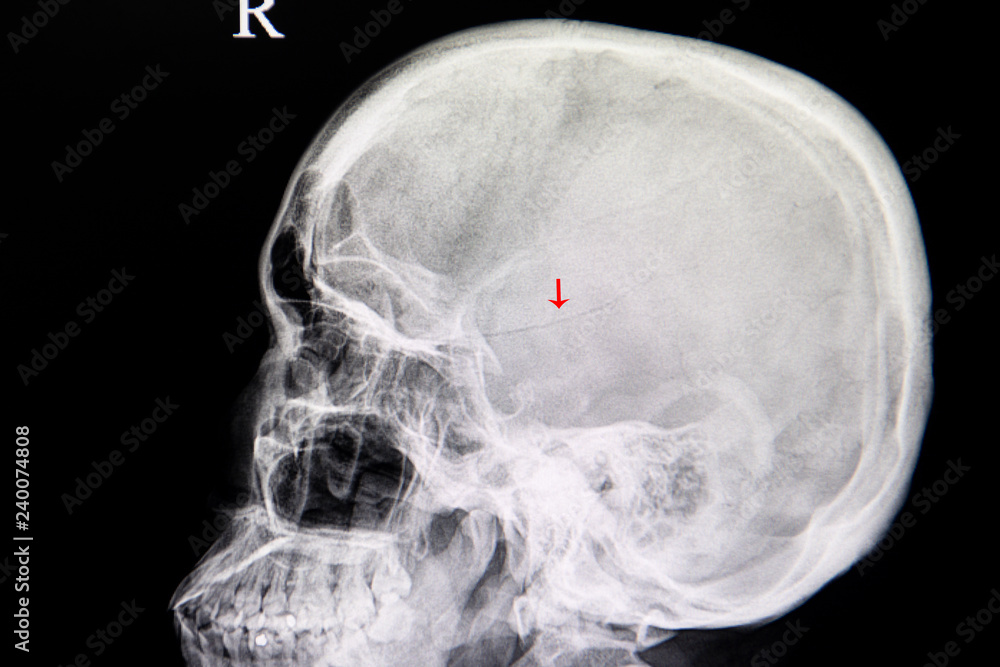

xray image of a patient with linear fracture skull from traumatic Basilar Skull Fracture In Meningitis Basilar skull fractures predispose patients to meningitis because of the possible direct contact of bacteria in the paranasal sinuses,. Skull base fractures increase the risk of developing meningitis because of the possible contact of bacteria in the nose, throat, or ear with the central nervous system. The majority of patients in whom meningitis develops as a complication of closed head. Basilar Skull Fracture In Meningitis.